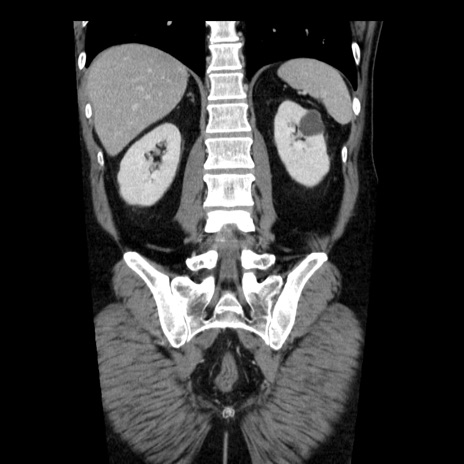

症例29(冠状断像)

【症例】40歳代男性

【現病歴】2日前から胃痛あり。徐々に周期的な激痛に変化した。本日になっても激痛があるため受診。

【身体所見】意識清明、BT 38-39℃台あり、腹部:膨満、やや硬、右下腹部に圧痛あり。

【データ】WBC 8500、CRP 23.26